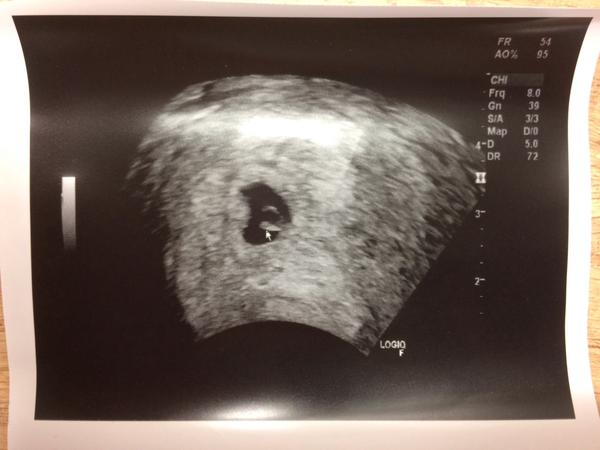

@bobulkapetka Gratulujem ti super ze uz bolo aj srdiecko vidiet!!!Pekne tehulkovanie bez komplikacii!!! Ja som zvedava co zajtra my... Mne sa prerezava zub mudrosti a cele mi to zapuchlo tak mi to dasno nasilu otvaraju a akoze liecia... Lenze ja to mam horsie a horsie..

@adkaaa Dakujem 🙂 neboj zajtra aj ty uvidis ❤️ Potom hod foto. A nech ta ten zub uz prestane trápiť!

@bobulkapetka Ahojte tak vsetko je v poriadku, bublinka podrastla aj zltkovy vacok bolo vidiet... Na srdiecko si musime este pockat, tak ideme znova buducu stredu... Dufam ze uz bude aj to... Zuby som spomenula aj pripadne antibiotika a povedal mi dr.ze ked treba tak nech nasadia...A stale mam aj zvysenu teplotu 37,5 a to je tiez normalne v tehotenstve....

@adkaaa tak daň teším ze je vsetko Ok. Uz nech len ten zub prestane trápiť. A neboj budúci týžden bude aj ❤️ A koľko má bublinka teraz?